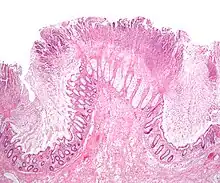

Una investigación importante en la evaluación de la colitis es la biopsia. Se extrae una muestra muy pequeña de tejido (generalmente de unos 2 mm) de la mucosa intestinal durante la endoscopia y un histopatólogo la examina al microscopio. Puede proporcionar información importante sobre la causa de la enfermedad y el alcance del daño intestinal.